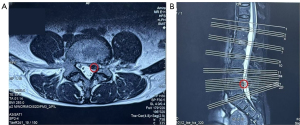

We decided to perform ultrasound-guided needle knife releasing of the ligamenta flava once every 7 to 10 days. After four treatments, the patient was examined, with the findings being as follows: negative sign on Kernig’s test, no numbness or pain in the lumbar and leg regions, and a VAS score of 3. We also used the 36-Item Short Form Health Survey (SF-36) of medical outcomes to assess the patient’s quality of life (Table 1). Review MRI confirmed significant morphological changes in the responsible nerve root after treatment and disappearance of the spinal canal indentation (Figure 2).